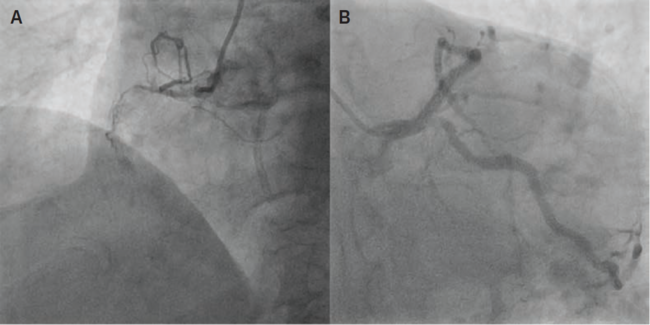

Echocardiography revealed severe aortic stenosis, with a valve area of 0.6 cm², a mean gradient of 34 mmHg, and a peak velocity of 4 m/s, consistent with severe AS. Coronary angiography demonstrated severe coronary artery disease, including left main (LM) stenosis and multivessel CAD (Figure 1). Given the complexity of his coronary pathology, he was deemed unsuitable for traditional coronary artery bypass grafting (CABG) due to the high surgical risk associated with both his coronary disease and comorbidities.

Coronary angiography revealed critical stenosis of the left main coronary artery and significant disease in the left anterior descending (LAD) and left circumflex (LCx) arteries. A double-barrel technique was successfully employed to stent the left main bifurcation, with optimal angiographic results achieved.

After coronary revascularization, the TAVR was performed using a 26 mm Sapien 3 Ultra valve (Edwards Lifesciences), which was deployed successfully with no complications (Figure 4).